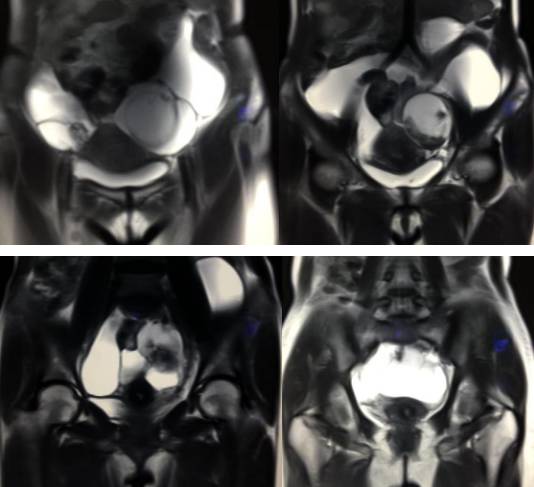

MR检查:

病理结果:黄体血肿

黄体血肿为正常排卵过程中,卵泡层破裂,引起出血,较多的血液潴留在卵泡或黄体腔内形成血肿。

正常黄体直径为15mm左右,以后转变为白体,并在下一个周期的卵泡期自然消退。若黄体内出血量较多,则形成黄体血肿,或称黄体内出血,出血性黄体。黄体血肿多为单侧,一般直径为40mm,偶可达100mm,黄体血肿被吸收后可导致黄体囊肿,较大的血肿破裂时可出现腹腔内出血,剧烈腹痛、少量阴道流血和腹膜刺激征,不易与宫外孕区别。

黄体血肿早期:囊内出血较多时,表现为卵巢内近圆形囊肿,囊壁厚,内壁粗糙。

黄体血肿中期:黄体血肿内血液凝固,部分吸收,囊壁变薄而,内壁光滑。

黄体血肿晚期:血液吸收后囊肿变小,转变为白体,内部回声呈实性稍高回

声,与周围卵巢策划分界不清,面靠彩超显示其周围环状血流判断,当血液完全吸收后形成黄体囊肿,囊壁变得光滑,与卵巢其他囊肿难以区分。

根据时间不同MR信号也有所不同,TIWI脂肪抑制序列可以鉴别脂肪和出血。